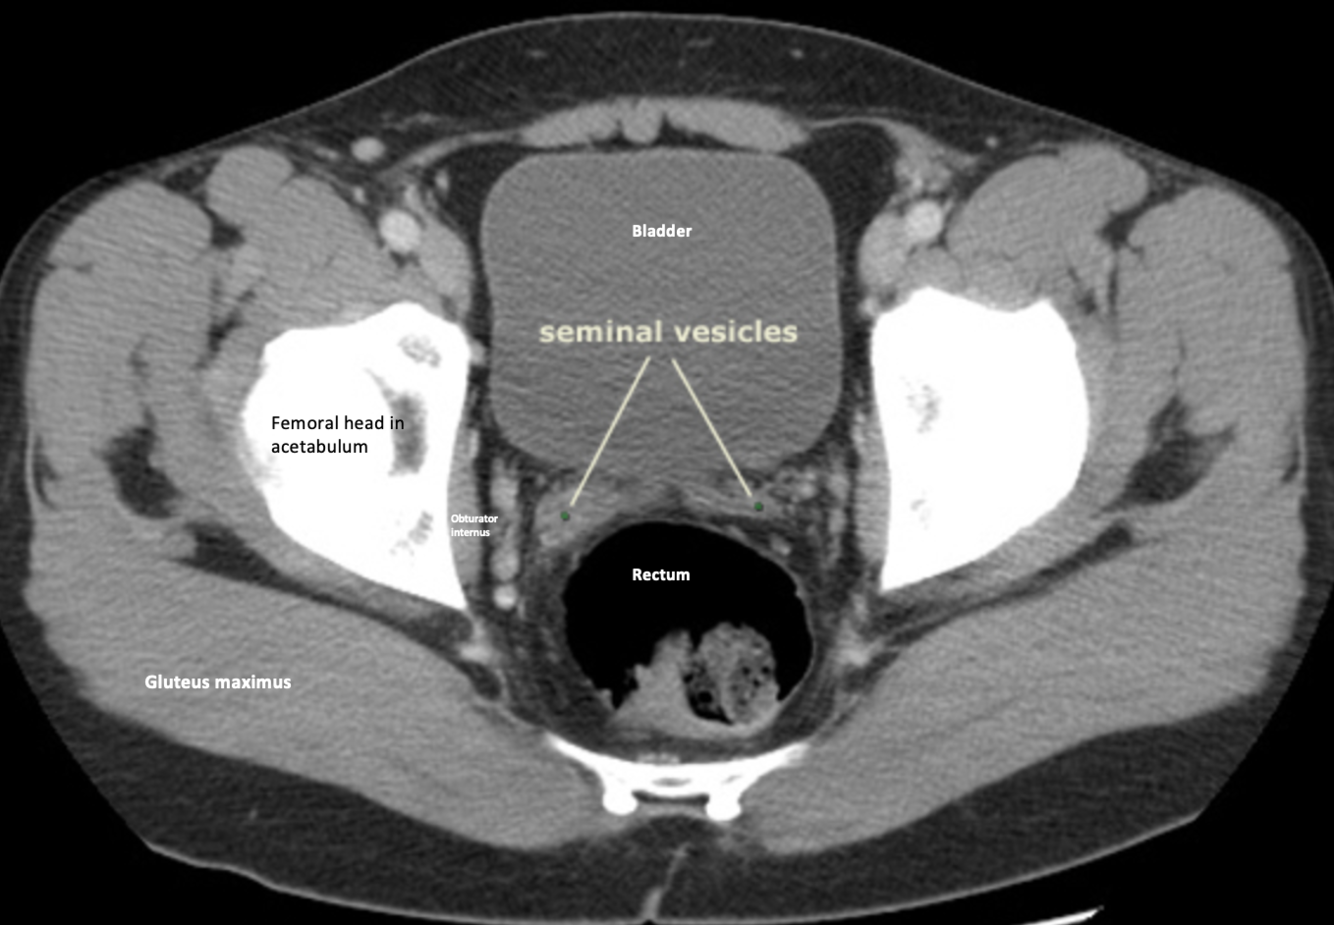

CT male pelvis, axial view

Calcification within the vascular structures; small bit of calcifications in vas deferes

Yellow arrows: vas deferens running over the external iliac vessels

(CT axial of male pelvis)